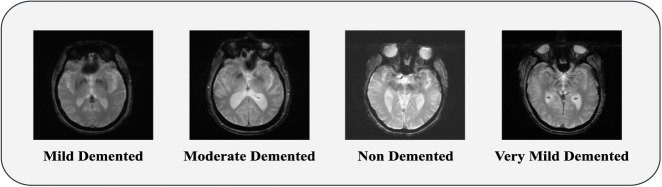

Methods: This study proposes transfer learning-based methods for extracting features from MRI scans for multi-class classification of different AD categories. Four transfer learning-based feature extractors, namely, ResNet152V2, VGG16, InceptionV3, and MobileNet have been employed on two publicly available datasets (i.e., ADNI and OASIS) and a Merged dataset combining ADNI and OASIS, each having four categories: Moderate Demented (MoD), Mild Demented (MD), Very Mild Demented (VMD), and Non Demented (ND).